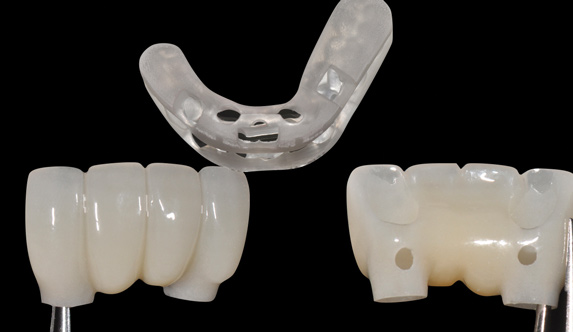

Fig 16. Presurgical design and fabrication of restorative components based on virtual implant position allow for possible minor angle/linear deviations (Fig 16 through Fig 18). Component options are broad and may include a custom healing abutment and bondable polymethyl methacrylate restoration; a single restoration with an engaging or non-engaging base; provisional fixed partial dentures (Fig 19), which can be indexed intraorally to prepared temporary abutments; or a full-arch restoration to be indexed intraorally to prepared temporary abutments.

Figure 16

Fig 17. Presurgical design and fabrication of restorative components based on virtual implant position allow for possible minor angle/linear deviations (Fig 16 through Fig 18). Component options are broad and may include a custom healing abutment and bondable polymethyl methacrylate restoration; a single restoration with an engaging or non-engaging base; provisional fixed partial dentures (Fig 19), which can be indexed intraorally to prepared temporary abutments; or a full-arch restoration to be indexed intraorally to prepared temporary abutments.

Figure 17

Fig 18. Presurgical design and fabrication of restorative components based on virtual implant position allow for possible minor angle/linear deviations (Fig 16 through Fig 18). Component options are broad and may include a custom healing abutment and bondable polymethyl methacrylate restoration; a single restoration with an engaging or non-engaging base; provisional fixed partial dentures (Fig 19), which can be indexed intraorally to prepared temporary abutments; or a full-arch restoration to be indexed intraorally to prepared temporary abutments.

Figure 18

Fig 19. Presurgical design and fabrication of restorative components based on virtual implant position allow for possible minor angle/linear deviations (Fig 16 through Fig 18). Component options are broad and may include a custom healing abutment and bondable polymethyl methacrylate restoration; a single restoration with an engaging or non-engaging base; provisional fixed partial dentures (Fig 19), which can be indexed intraorally to prepared temporary abutments; or a full-arch restoration to be indexed intraorally to prepared temporary abutments.

Figure 19

From the data and collaboration in steps 1 through 3, surgical guides can be fabricated for static surgery, and when indicated, prosthetic components, such as custom healing abutments, provisional crowns, or fixed partial dentures, can be produced for delivery at the time of surgery to guide soft-tissue healing. The static approach, better known as computer-guided surgery, refers to the use of tissue-tooth or soft- and hard-tissue-supported surgical templates. In essence, the virtual implant position planned from the CBCT, IOS, and face-in data sets is reproduced. The guide is produced with master cylinders (portals) through which the osteotomy preparation drills are introduced, and in full-guidance cases, the delivery of the implant is carried out (Figure 14 and Figure 15). Dynamic guided surgery or computer "navigation" traces the virtual implant position directly from CBCT data and employs motion tracking or real-time tracking technology to prepare the implant osteotomy. This makes it possible to determine the actual position of the surgical drill on the reconstructed 3D image provided by the CBCT. The surgeon is guided to the position that was planned preoperatively while he or she performs the surgical procedure. Examples of dynamic navigation systems are Navident (ClaroNav, claronav.com), X-Guide Dynamic 3D Navigation (X-Nav, x-navtech.com), Image Guided Implant (IGI) Dentistry System (Image Navigation, image-navigation.com), Inliant® (Navigate Surgical, navigatesurgical.com), and YOMI®, a robotic haptic guidance system (Neocis, neocis.com).

One of the biggest advantages of the digital workflow is being able to take the planning of the implant and transfer that data to the restorative software. This uses the planned position of the implant and allows the laboratory to fabricate provisionals or custom healing abutments before the surgery, saving the dentist chairtime and making the surgery less stressful. As the workflow improves and software interfaces become more open, it will make this part more predictable. At the moment, there is not one specific recognized workflow for all of the restorations, and the necessary workarounds can sometimes lead to inaccuracies. Any laboratory that pushes the capabilities of the current software should do this only with experienced dentists.

The introduction of prefabricated provisional or transmucosal components enables dentists to better control and realize the benefits of tissue guidance, especially in immediate implant placement protocols (Figure 16 through Figure 19).13 While immediate provisionalization or tissue guidance is not a new concept, the ability to preplan and fabricate these appliances before surgery is an important evolution tied to the digital workflow. Historically, restorative components such as custom healing abutments, provisional crowns, or fixed partial dentures were either made chairside "intrasurgically" or impressions were taken for delayed delivery.